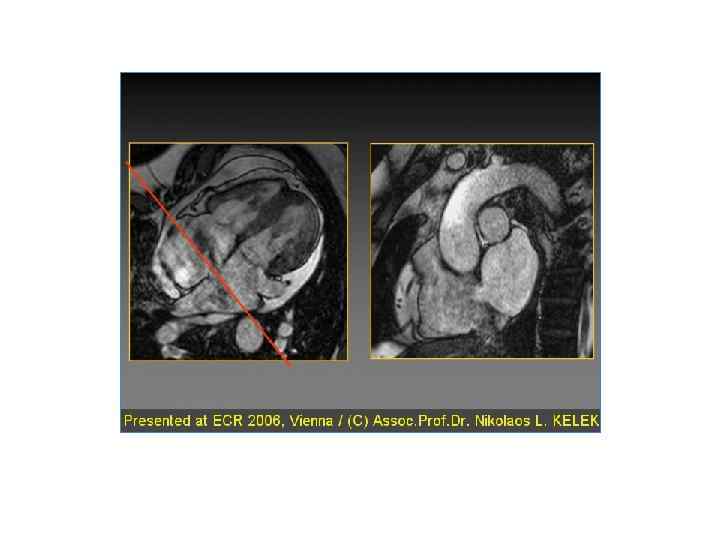

Основные методы послойного исследования сердца: магнитный резонанс, компьютерная томография, изотопная томография

Магнитно – резонансная томография • Наиболее современный и информативный метод исследования • Лучевая нагрузка на пациента и врача отсутствует • Главный недостаток – относительно высокая стоимость исследования

МРТ срез грудной полости